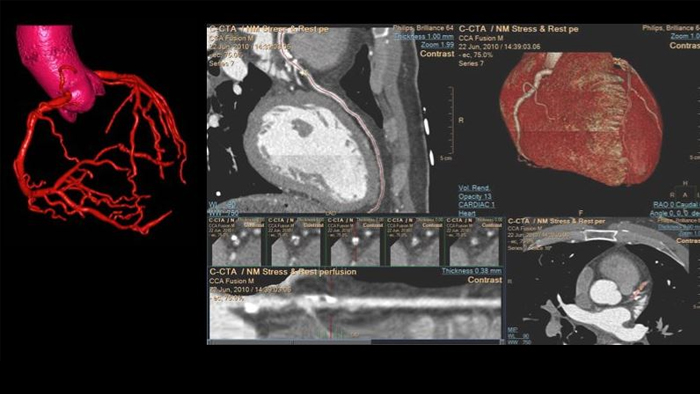

IntelliSpace Portal

Review, analyze and quantify clinical information from different modalities and for various clinical indications with AI-enabled 3D models, maps and other quantitative tools.

Cardiovascular Workspace*

Provide a single point of access to patient’s cardiovascular diagnostic information and multi-modality images at full diagnostic quality, including prior exams, as well as findings, measurements, and reports.